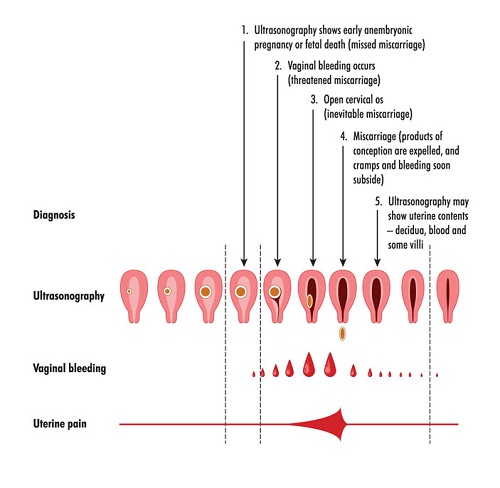

Is Spotting normal during Pregnancy? | Styles At Life